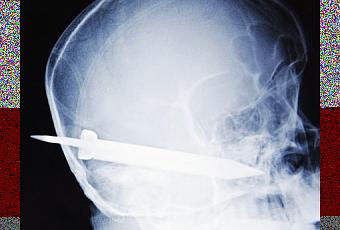

Xi'an, Chine - Un homme a été poignardé à la tête par son père avec une lame de 13 cm.

Wen Wen, 38 ans, est entré dans l'hôpital de Xi'an avec la lame d'un couteau entièrement enfoncée dans son crâne. Seul le manche dépassait. Une infirmière des urgences s'est évanouie quand elle l'a vu à la réception avec l'objet sortant de sa tête. L'homme totalement conscient répondait à des questions concernant l'accident. La lame du couteau était entrée au-dessus de l'oreille droite, passée près de la cavité nasale avant de ressortir par la bouche. Aucun vaisseau sanguin, artère ou nerf important n'a été touché.